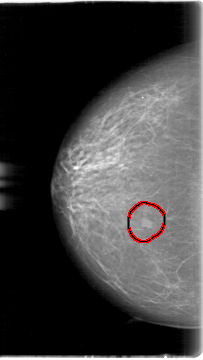

D_4068_1.LEFT_CC

FILE: D_4068_1.RIGHT_CC.OVERLAY

TOTAL_ABNORMALITIES 1

ABNORMALITY 1

LESION_TYPE MASS SHAPE IRREGULAR MARGINS OBSCURED

ASSESSMENT 0

SUBTLETY 4

PATHOLOGY BENIGN

TOTAL_OUTLINES 1

BOUNDARY